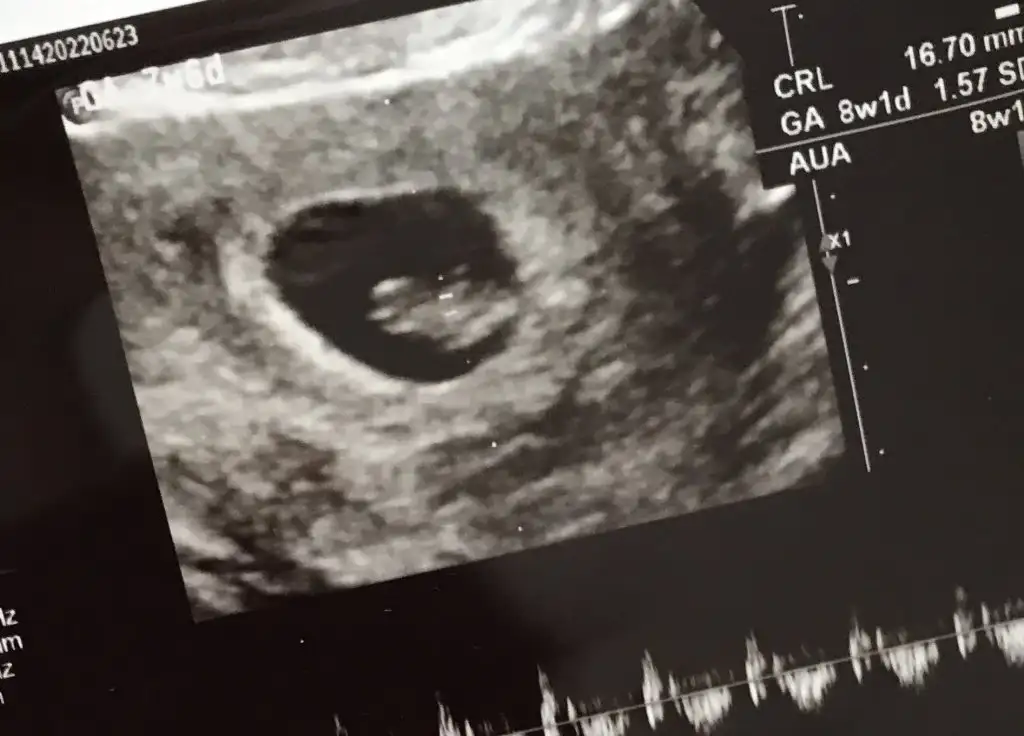

Merhaba 7 buçuk haftalık tahmin ederseniz sevinirim☺️

Eklentiler

• IMG-20220628-WA0005.webp

IMG-20220628-WA0005.webp

21,7 KB · Görüntüleme: 67